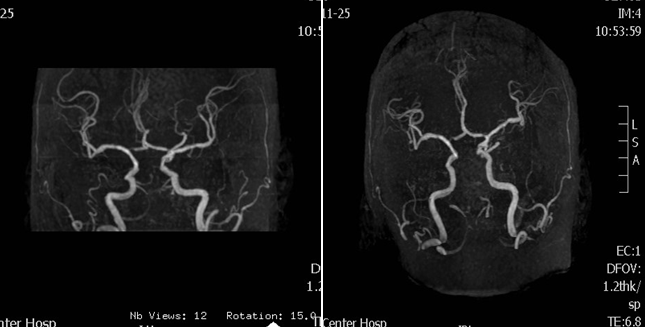

入院影像检查

导丝怎么扩【载药时代 球扩天下】NOVA DES®颅内药物洗脱支架在基底动脉近端重度狭窄的应用—西安市中心医院使用体会一例!_https://www.jmylbn.com_新闻资讯_第4张

MRA

导丝怎么扩【载药时代 球扩天下】NOVA DES®颅内药物洗脱支架在基底动脉近端重度狭窄的应用—西安市中心医院使用体会一例!_https://www.jmylbn.com_新闻资讯_第5张

DWI

重要影像结论:双侧小脑半球、脑干、右侧枕叶多发脑梗死;基底动脉、右侧大脑后动脉闭塞。

病变部位:基底动脉近段

远端正常血管直径(mm):2.45

狭窄处最小直径(mm):0.40

病变长度(mm):4.08

狭窄度(%):84%